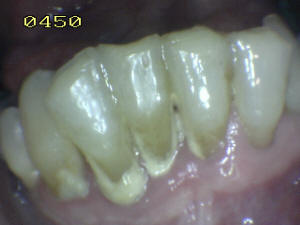

Hay dos zonas críticas, que hay que tener en cuenta para realizar un cepillado periódico. Una es la cara vestibular (ver foto 1),  la cara lingual de los dientes anteroinferiores (ver foto 2 ) y la cara vestibular de los 1ª molares superiores.

Es en estas zonas dónde comienza a formarse el sarro dental, la única forma que Ud. puede evitar la formación de tártaro es cepillando diariamente sus dientes.